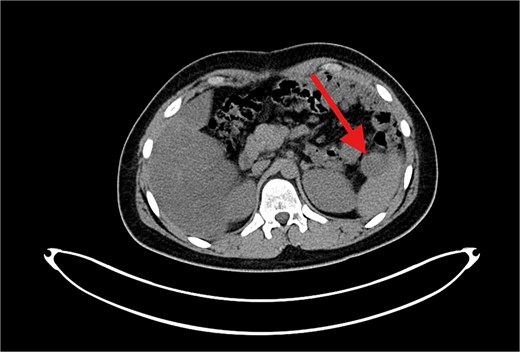

The patient underwent left lateral hepatectomy and cholecystectomy following diagnosis. Histopathology confirmed undifferentiated embryonal sarcoma (UES) of the liver with a 1 mm clear margin (Fig. 1); immunohistochemistry supported the diagnosis. The gallbladder showed chronic cholecystitis, and the lymph nodes were tumor-free. Postoperative imaging after two months revealed a recurrent mass near the stomach (Fig. 2), confirmed as recurrent UES by biopsy. Re-excision showed extensive necrosis and peritoneal infiltration. Positron emission tomography – computed tomography (PET-CT) later identified peritoneal and mesenteric metastases (Fig. 3). Follow-up PET-CT also revealed multiple small hypermetabolic hepatic nodules in addition to peritoneal and mesenteric lesions, indicating intrahepatic disease recurrence. Six cycles of chemotherapy resulted in near-complete resolution of metabolic lesions, with minimal residual activity. Follow-up imaging showed near-complete resolution of hepatic nodules, with only one residual, non-suspicious tiny nodule. After additional chemotherapy and targeted therapy cycles, PET-CT revealed new focal hypermetabolic activity near the splenic flexure, anterior to the spleen, raising concern for recurrence (Fig. 4). The patient underwent omentectomy and splenectomy. Histopathology confirmed metastatic UES in a 2.5 cm splenic lesion with hemorrhage and necrosis, and a 0.4 cm omental nodule, both completely excised. A total of 15 chemotherapy cycles were completed. Post-treatment imaging showed a mixed-density lesion in the splenic bed with FDG uptake, possibly post-surgical, and a new hypermetabolic mesenteric nodule (Fig. 5). Magnetic resonance imaging showed a cystic post-surgical collection without enhancing lesions. Subsequent imaging revealed regression of the splenic bed lesion and resolution of the mesenteric nodule; however, a new hypermetabolic mesenteric density emerged (Fig. 6). The lesion was placed under active surveillance, with additional chemotherapy administered and repeat imaging scheduled to assess response. Bilateral axillary lymph nodes showed reactive hypermetabolism. The patient, having undergone hepatectomy, splenectomy, and multimodal therapy, remains under close surveillance with encouraging treatment response.

PET/CT scan showing a clear surgical bed. Almost complete metabolic resolution of the previous hypermetabolic abdominal deposits. Development of focal hypermetabolic activity just anterior and abutting the lower spleen pole, at the projection of splenic flexure of the descending colon, this lesion is nonspecific.